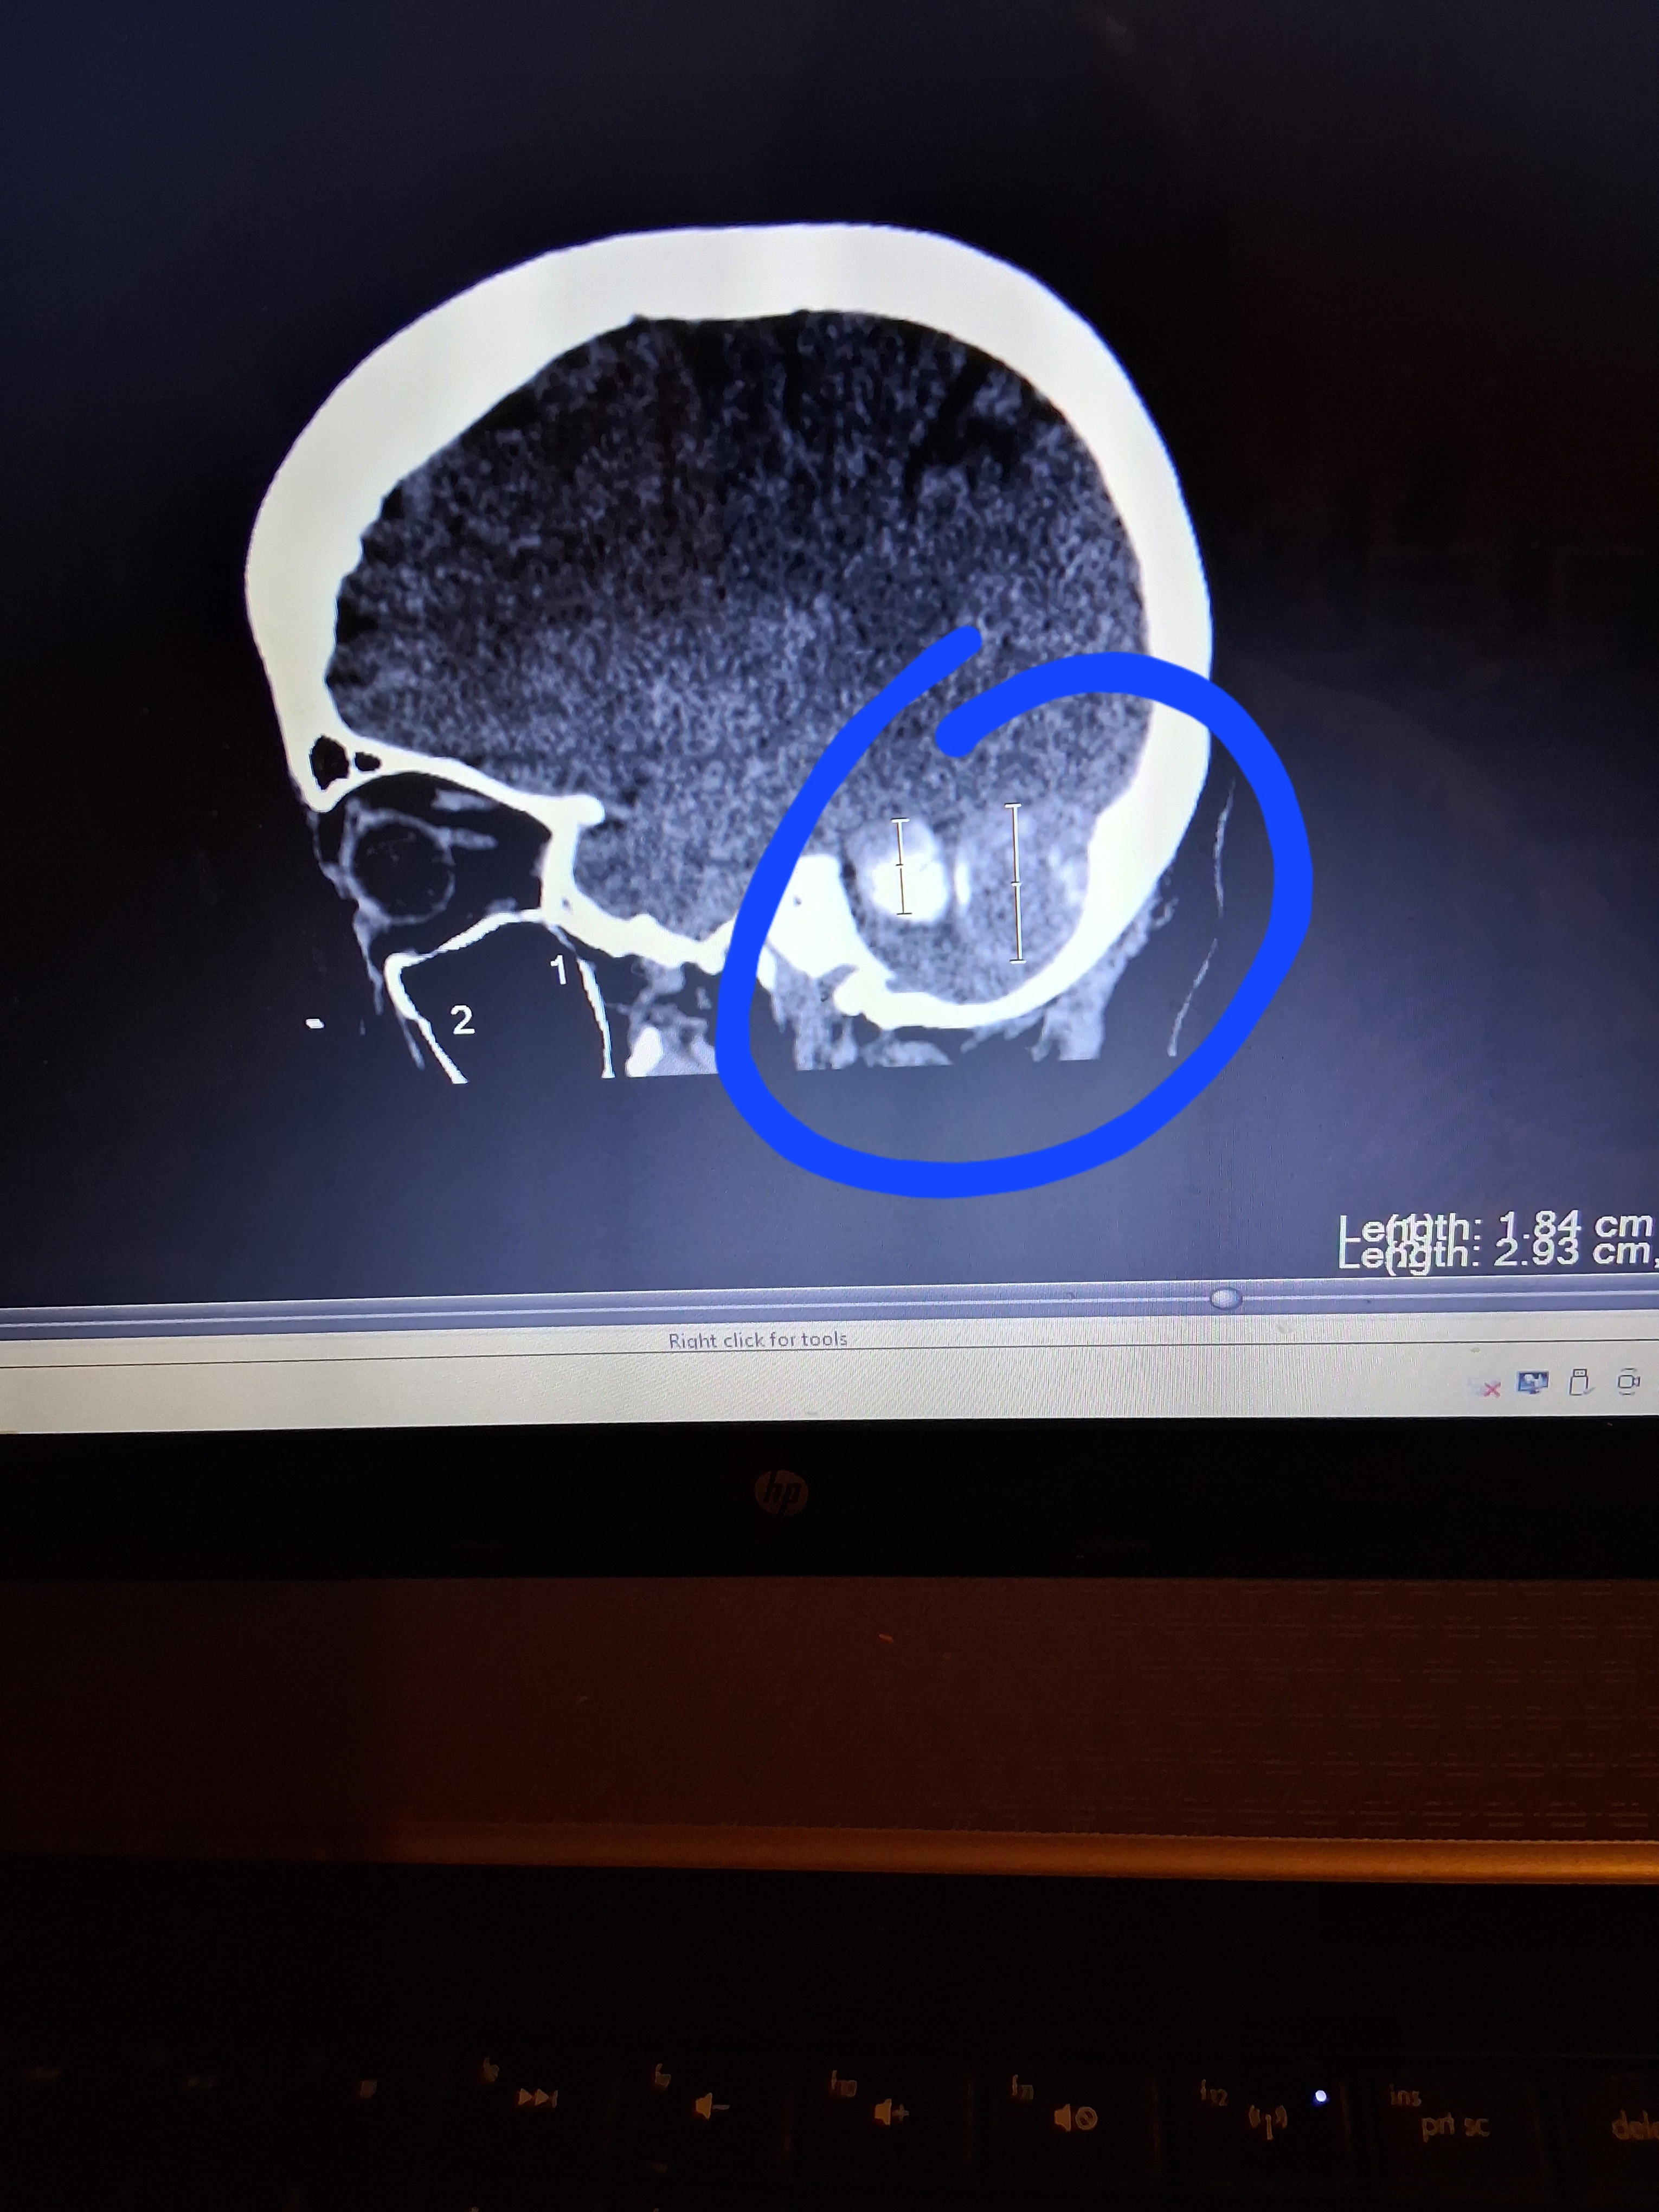

I have already 2 MRI's, and 2 C.T. scans, which showed 2 tumors, on the left side of my brain, and they are attached to one of the blood passages, on the left side of my head. I have 2 more scheduled MRI's, March 31st, and from there I will be scheduled to remove the MENINGIOMA.